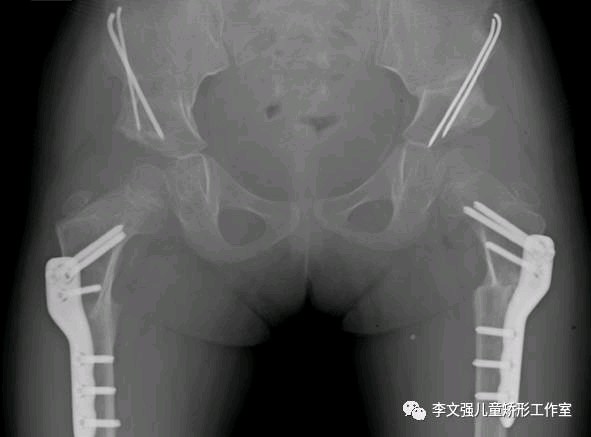

不同年龄应采用不同的治疗方法:(1).半岁以内:用Pavlik吊带治疗(2).半岁~1岁半:人类位石膏固定。一般治疗6~9个月。(3).1岁半~2岁:可以人类位石膏治疗或手术治疗。(4).2岁以上:需要手术治疗。分别是Salter手术、Pemberton手术和Chiari手术。

双侧DDH,行双侧Salter截骨矫形+股骨近端短缩去旋转截骨手术